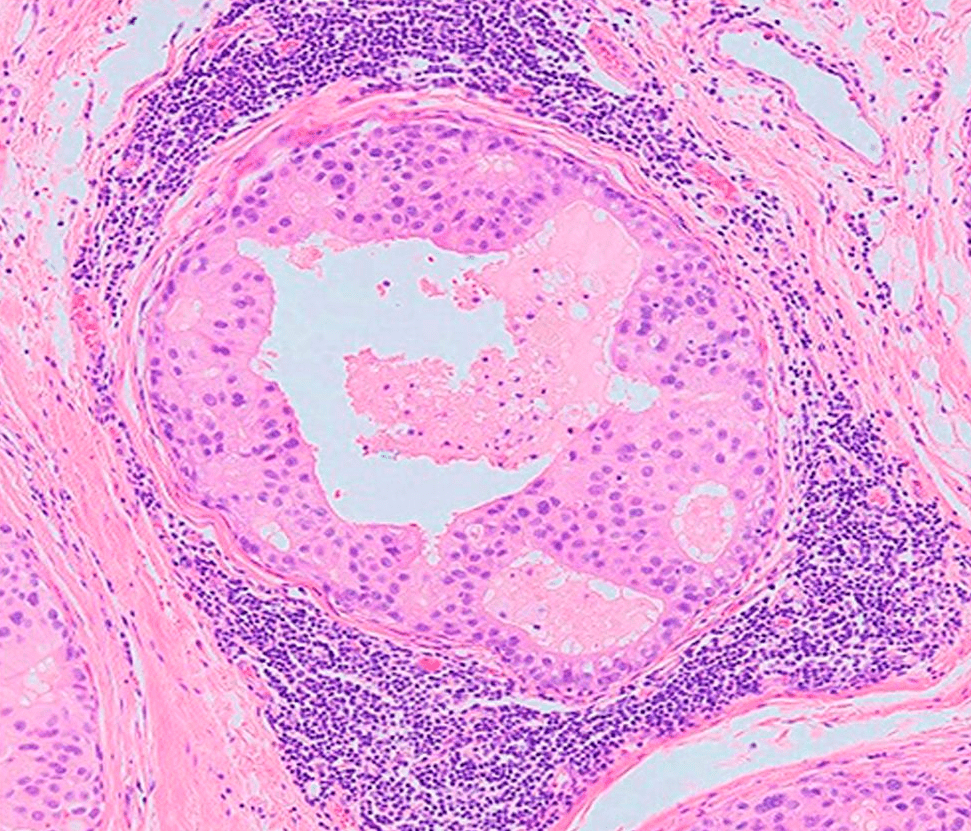

Исследование: микропрепарат молочной железы в медицине

Раздел: Снимки-откровения